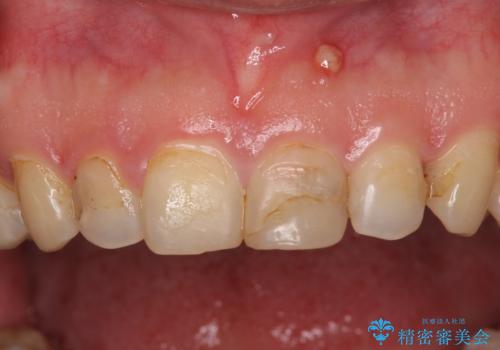

つぎはぎだらけの前歯をオールセラミッククラウンで自然な前歯に

- 前歯の色を気にして来院された患者様です。

むし歯で神経が取り除かれており、歯の変色と充填材の変色などにより、つぎはぎのような前歯となっていました。

膿の出口も認められたため、まずは根管治療を実施し、オールセラミッククラウンにて補綴治療を行うこととしました。